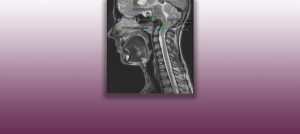

Institut Chiari & Siringomielia & Escoliosis de Barcelona is highly specialized neurosurgical center dedicated to the diagnosis and treatment of spinal and brain disorders, with a focus on the clinical concept of Filum Terminale Disease. Conditions treated include: